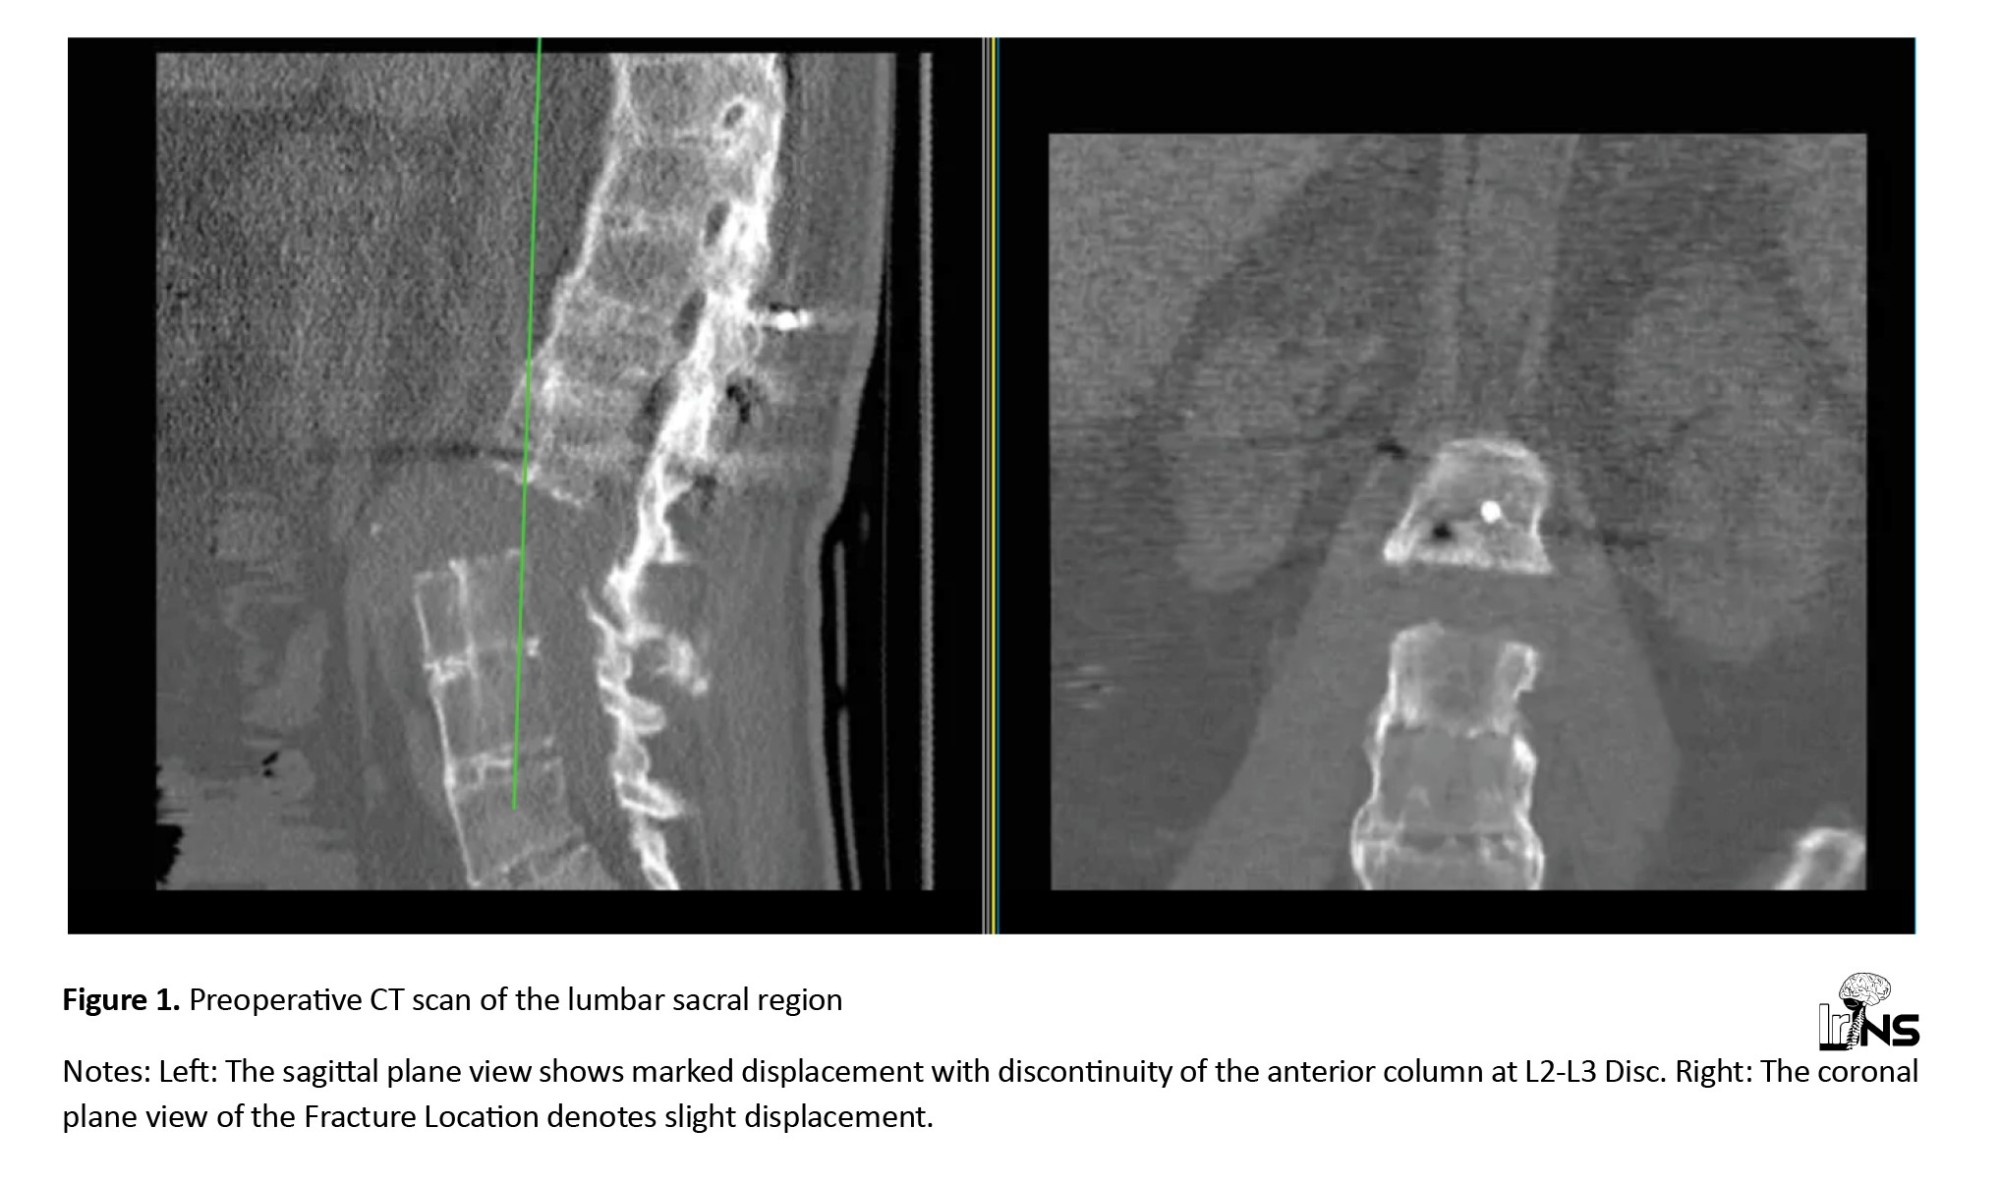

A whole-spine magnetic resonance imaging (MRI) was performed, which showed posterior ligamentous complex injury and disruption of the L2-L3 facet. The thecal sac was intact, and there was no intracanalicular fragment. The anterior longitudinal ligament was ossified and disrupted, while the posterior longitudinal ligament was injured but not completely torn (Figure 2).